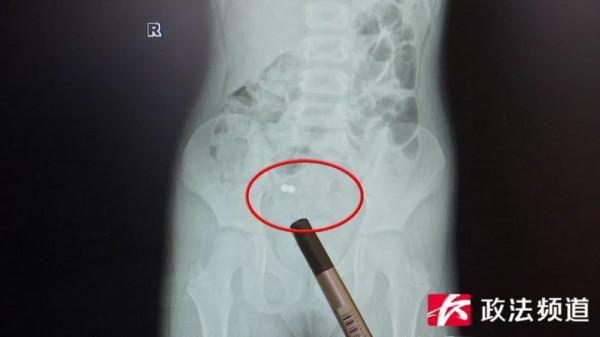

六歲女孩小雨(化名)剛上小學一年級,幾天前,她持續出現腹痛症狀,家長帶她前往當地醫院檢查時,孩子才承認自己半個月前誤吞過兩顆磁珠,由當地醫院轉診至湖南省兒童醫院後,醫生詳細檢查發現,小雨腸道內的確存在異物,需要立即做手術取出。

“他們之前在當地醫院拍了片子,發現孩子體內有磁珠,但是家長以為能自行排出,但是過了十多天一直沒有排出來,就轉診到了我們醫院。”湖南省兒童醫院普外一科主治醫師張甜說。

“經過檢查發現有兩處腸道穿孔,兩顆磁珠是吸在一起的,中間的腸壁已經糜爛了,因為兩顆磁珠把腸壁夾住了,如果不及時手術,可能出現瀰漫性的腹膜炎,感染會更嚴重。”湖南省兒童醫院普外一科主治醫師張甜表示。